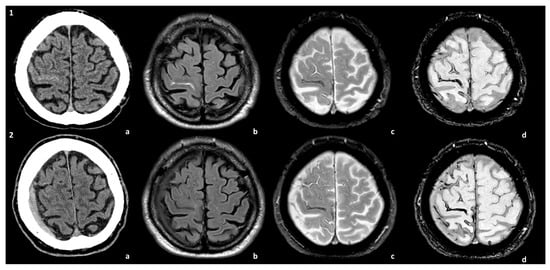

Some examples of the association of SDH with CAA and CAA-related inflammation are proposed in Figure 1 and Figure 2.

Figure 1. Spontaneous SDH in the natural history of a patient with CAA. The patient presented with TFNEs and convexal subarachnoid hemorrhage with cortical superficial siderosis (cSS) (panel 1). A right hemispheric SDH was found in the control MRI at 1 year (panel 2). The images are compared at the two time points of the natural history of the patient: (a) non-contrast CT, (b) axial Fluid-Attenuated Inversion Recovery (FLAIR) sequence, (c) T2* sequence, and (d) Susceptibility-Weighted Imaging (SWI) sequence.